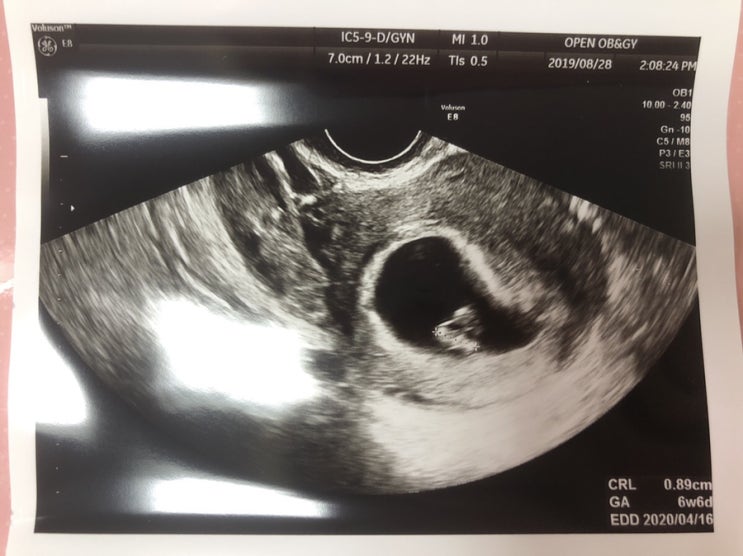

임신 6주 5일차

6주 5일차 피로가 안가셔서 갈색냉이 계속 나온다.. 출혈이 멎지 않아 회사 일주일 휴가 쓰고 (이 마저도 ...